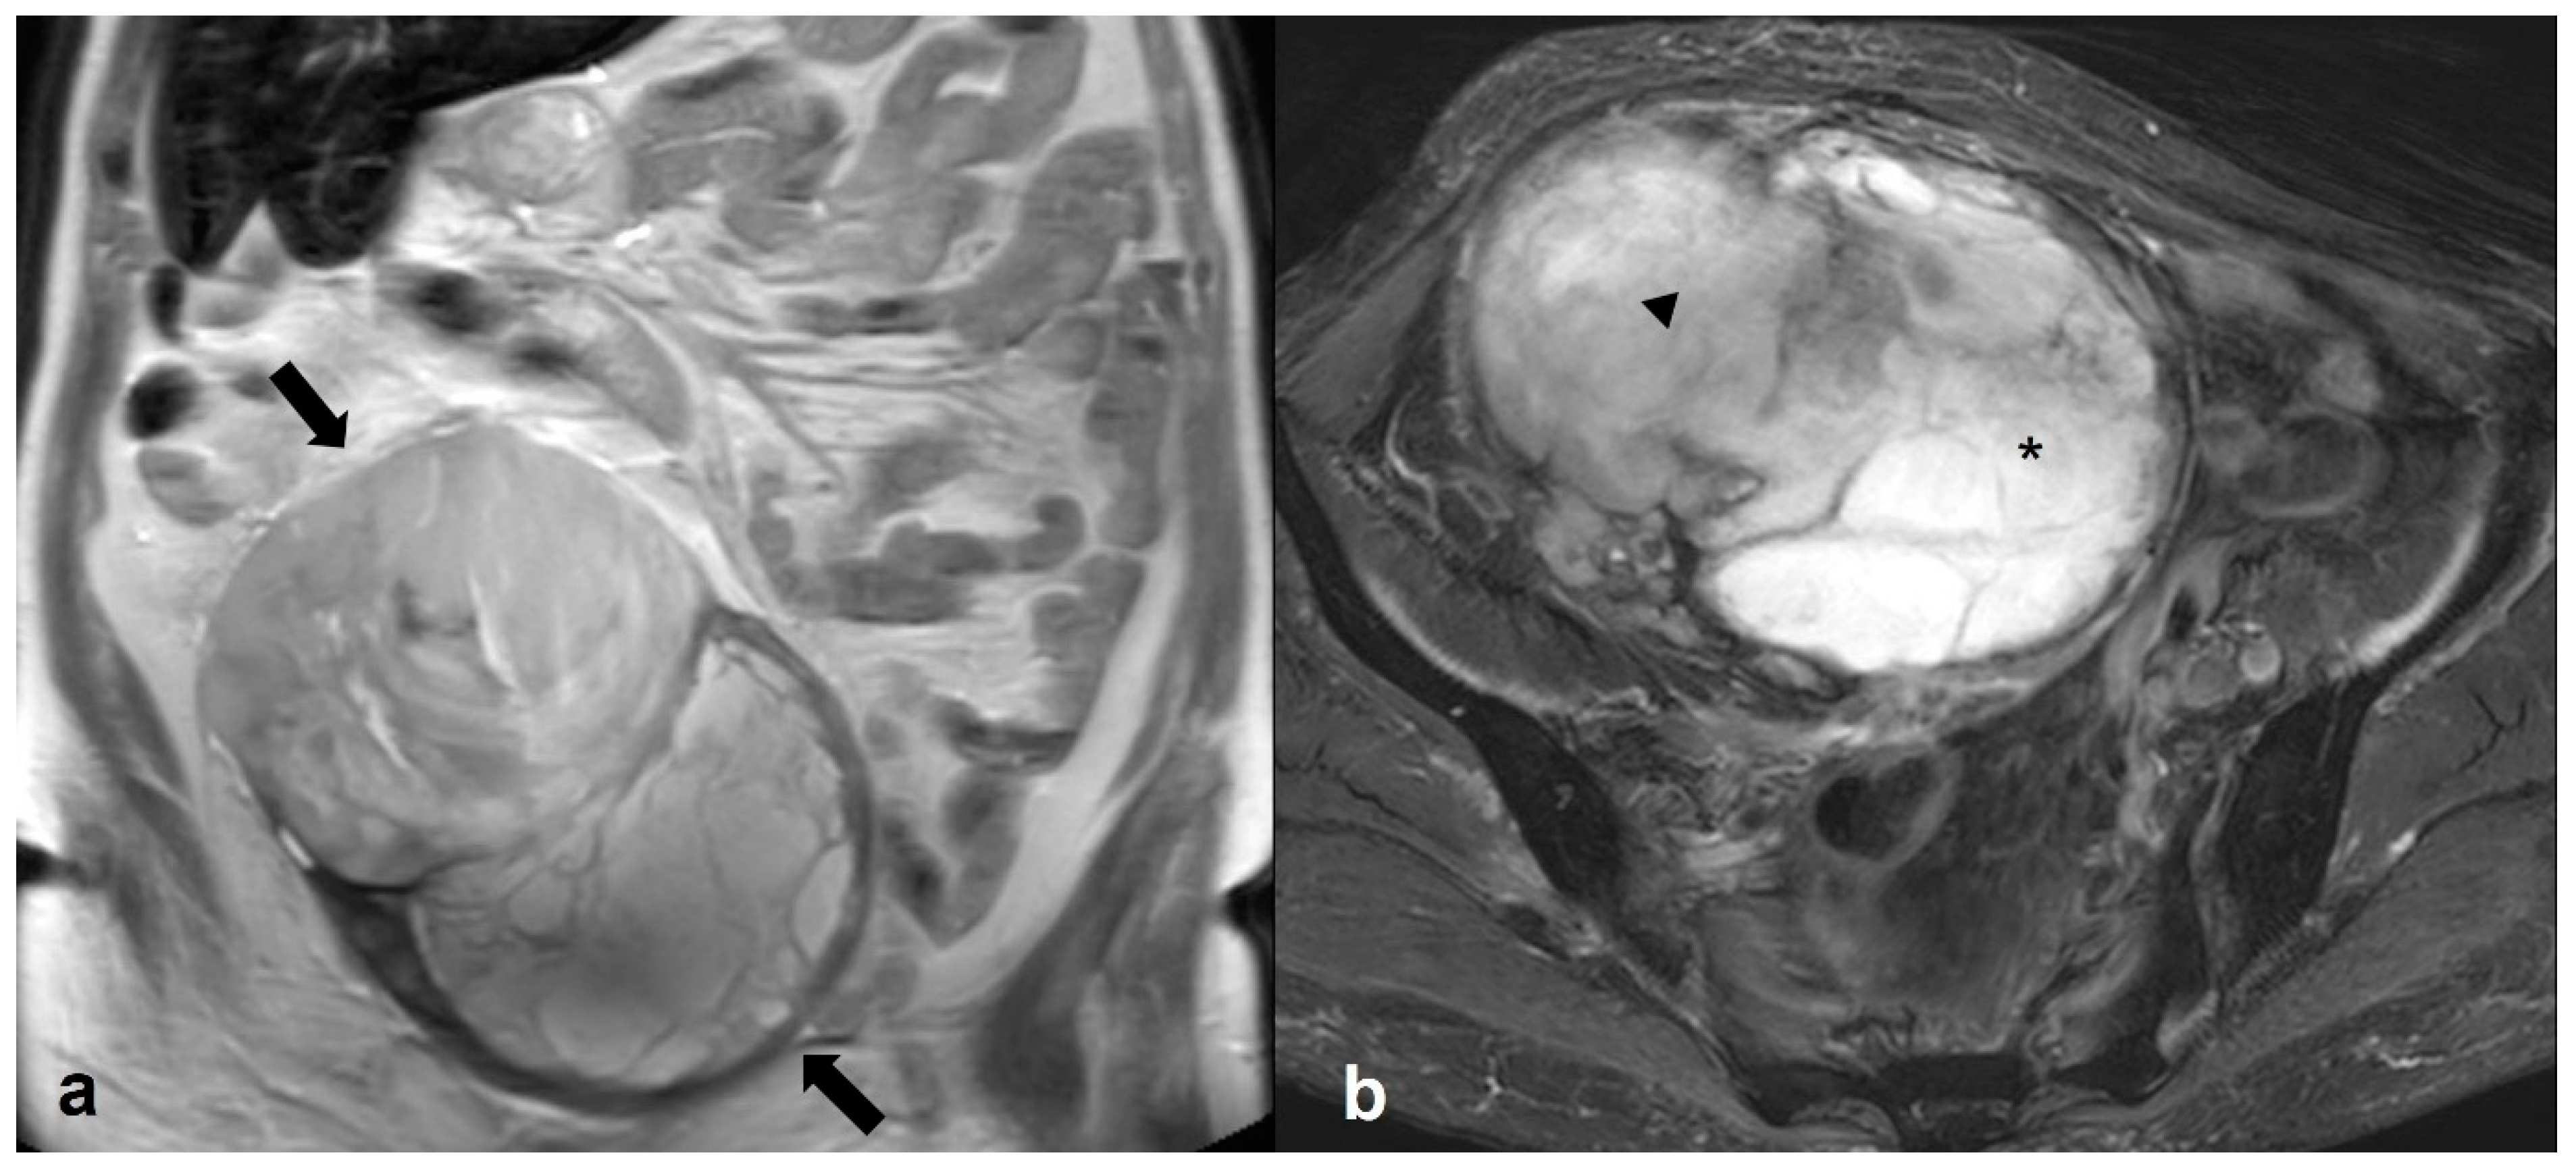

2.5.2. Decidualized Endometrioma

2.5.3. Epithelial Ovarian Cancer